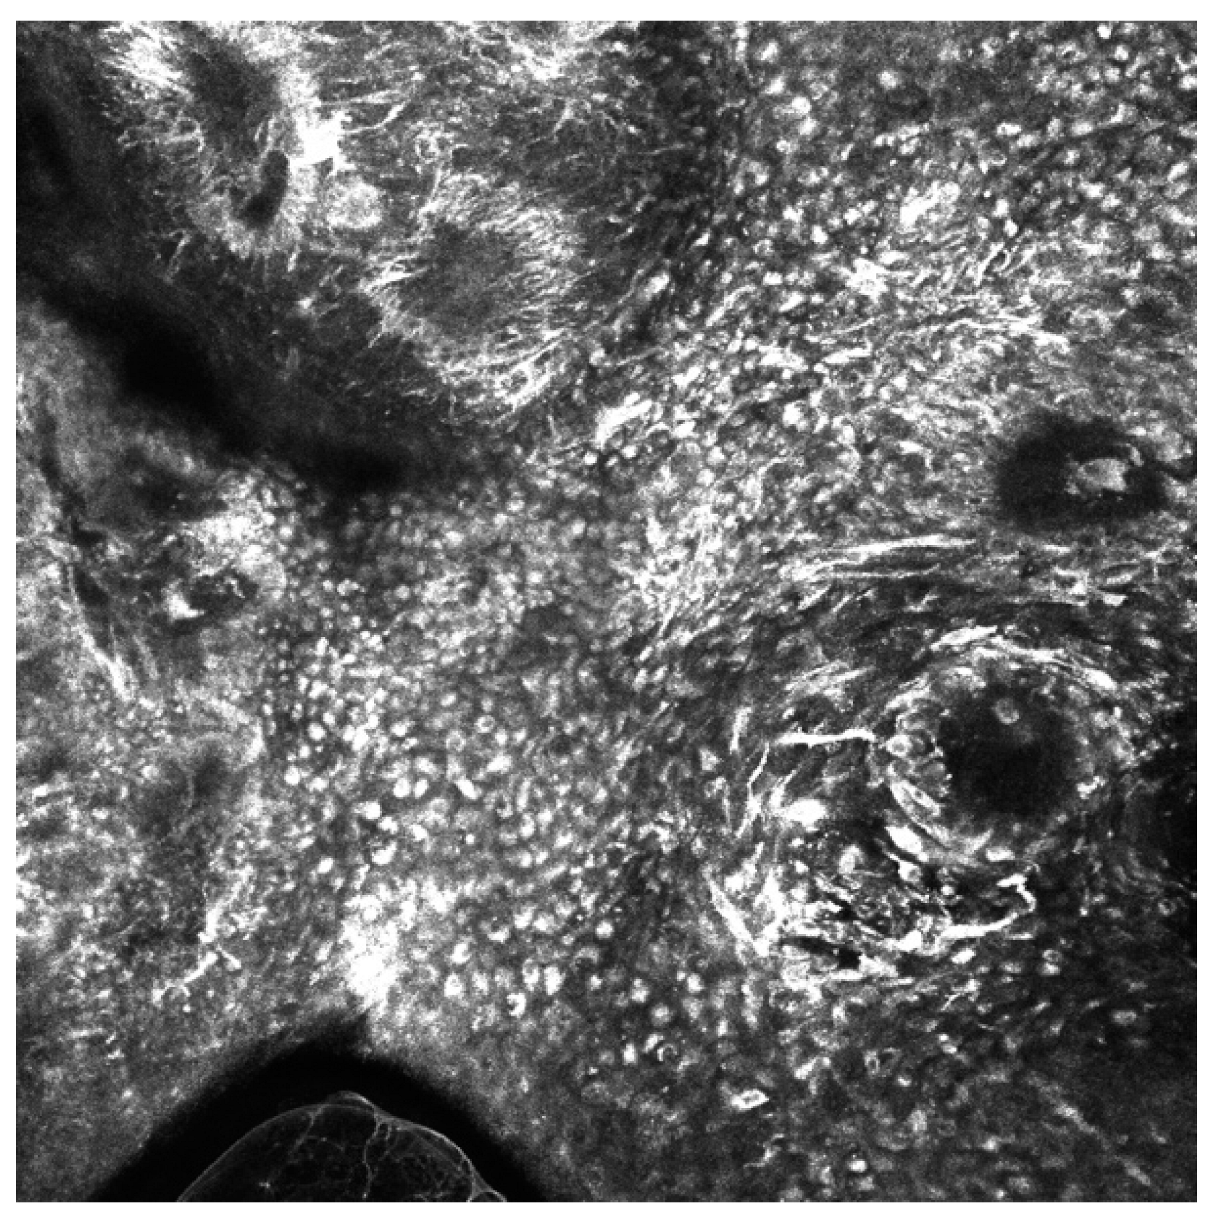

Figure 2.

Reflectance confocal microscopy mosaic of melanoma in situ taken at depth of the epidermis. There is an irregular cobblestone pattern, the presence of folliculotropism, and pleomorphic pagetoid cells (dendritic and round types) with numerosity greater than 10 per square millimeter. Image size: 1 mm × 1 mm.